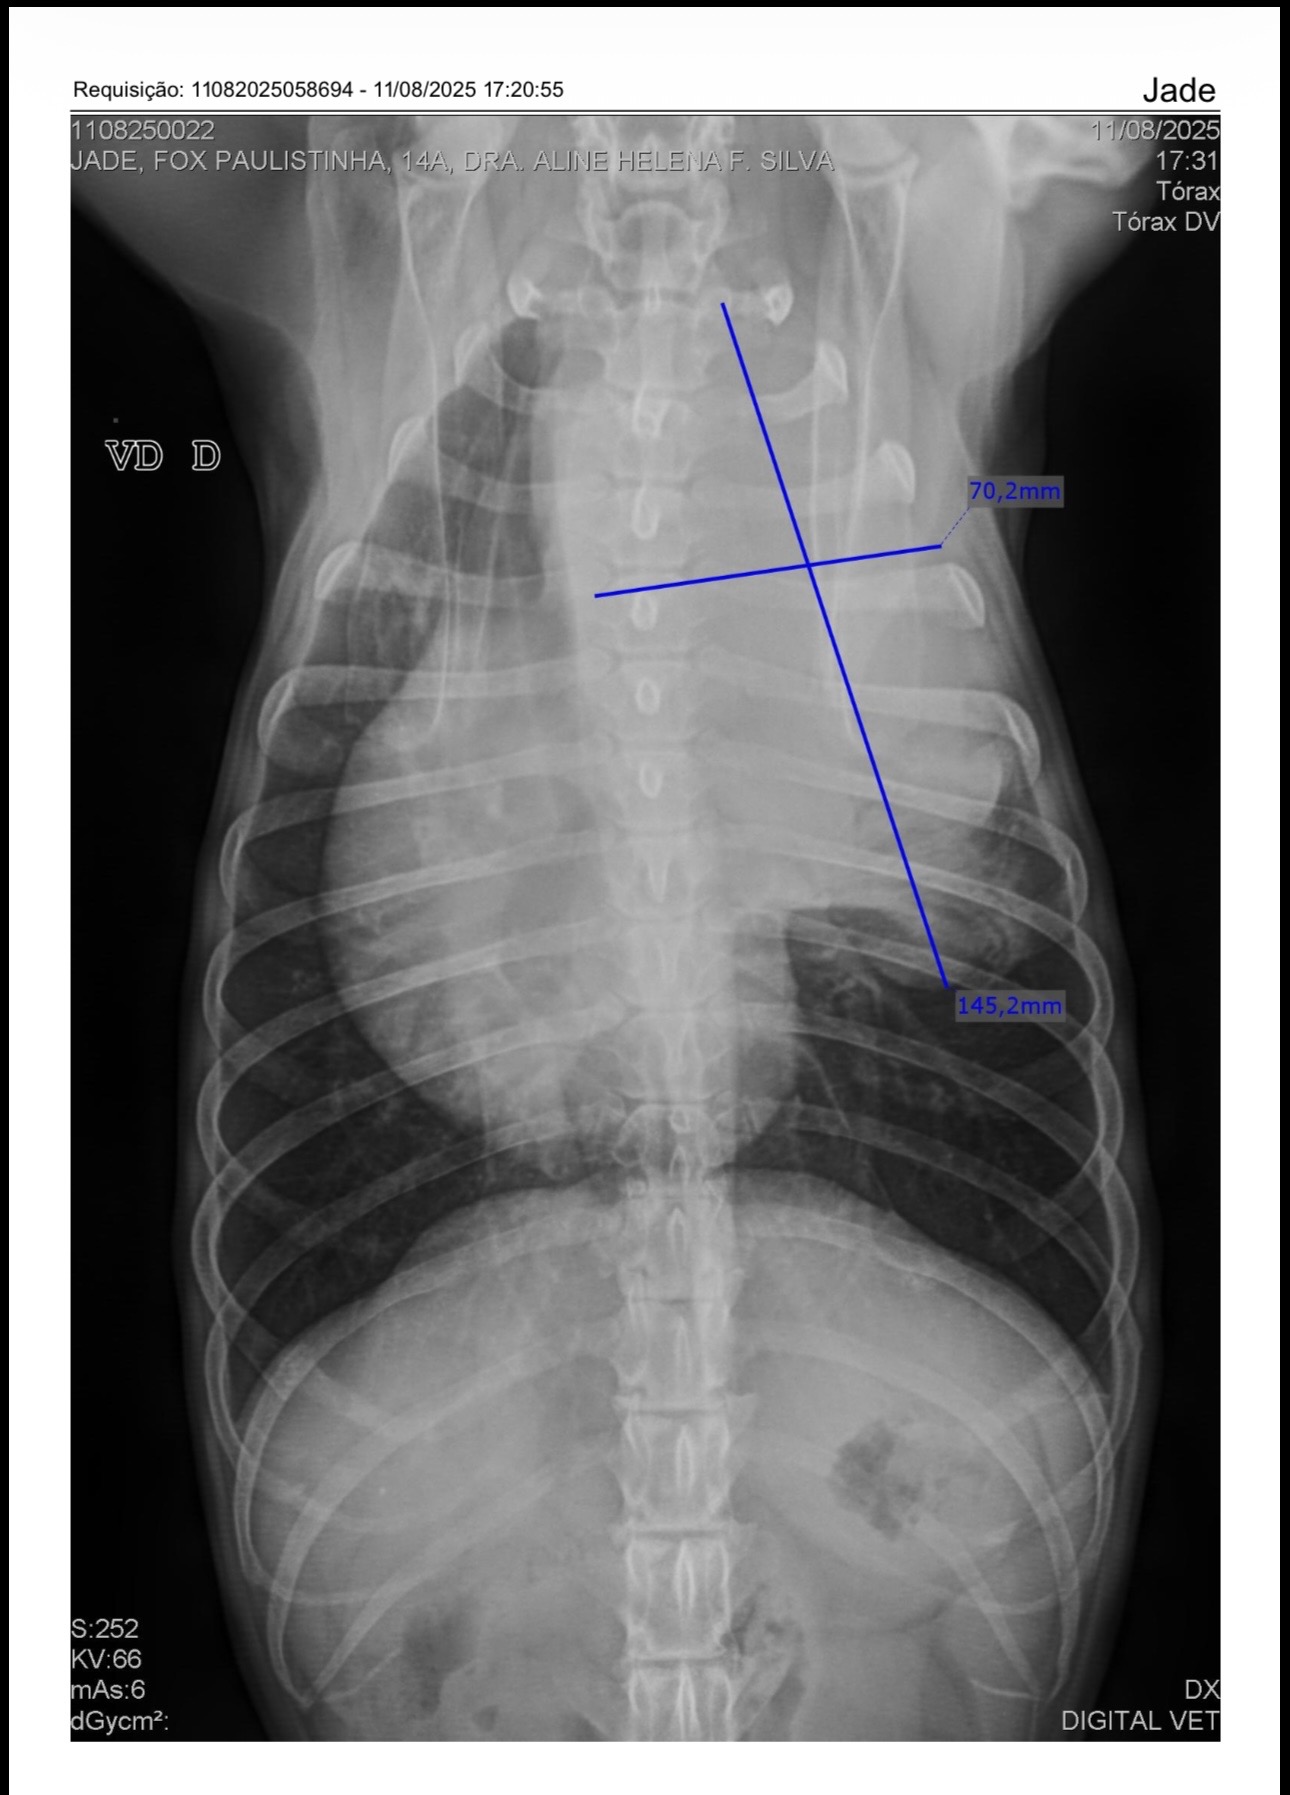

Tenho 15 anos e sempre vivi cercada de amor e cuidado da minha família. No ano passado, fomos surpreendidos com o diagnóstico de um carcinoma no mediastino, próximo ao coração e aos pulmões. Pela localização do tumor e pela minha idade, a cirurgia e tratamentos curativos não são possíveis.